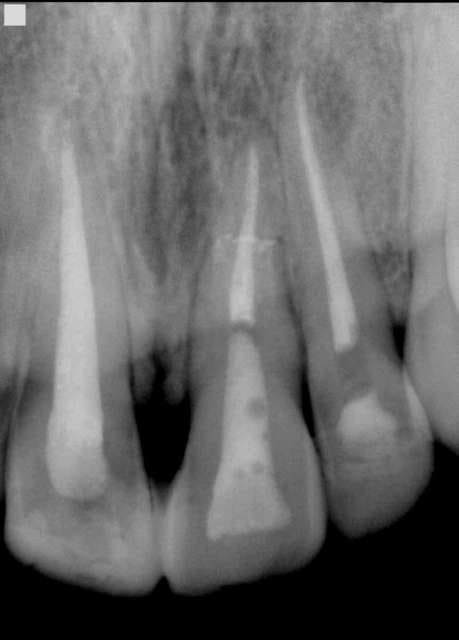

> Trauma, alvusion partielle (la dent était buccalée, a été replacée, mobilité,

> fracture au 1/3 apicale découverte lors de la visite d'endo d'urgence, 24h après

> l'accident.

> Les 2 autres endo datent de 2 ans, aussi trauma sportif.

D'abord , chapeau bas pour la qualité de la radio , et la précision de la mise en place de la lime

> D'abord , chapeau bas pour la qualité de la radio , et la précision de la mise en place de la lime

PS la digue est maintenue par des wedget, pour ne pas lèser la dent qui bougeait ! J'avais même coller au compo flow la 21 avec la 11 et la 22, por éviter le mouvement.

Patiente 17 ans

J'ai fait l'endo, et aviser qu'un jour, l'implant pourra être nécessaire...ou bridge tout céram